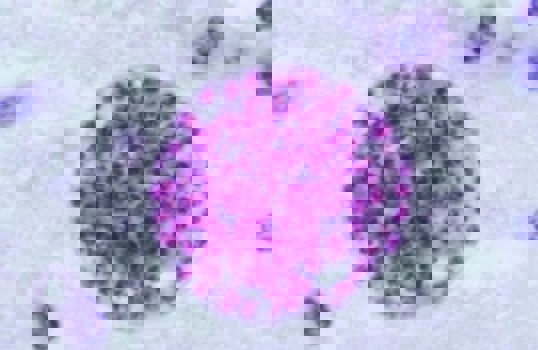

04:37 CH @ 25/11/2014Những năm gần đây, tại Việt Nam, một số bệnh giun, sán ngày càng hiếm gặp và một số bệnh có khả năng biến mất như: sán máng,Sán dải lùn Hymenolepis nana